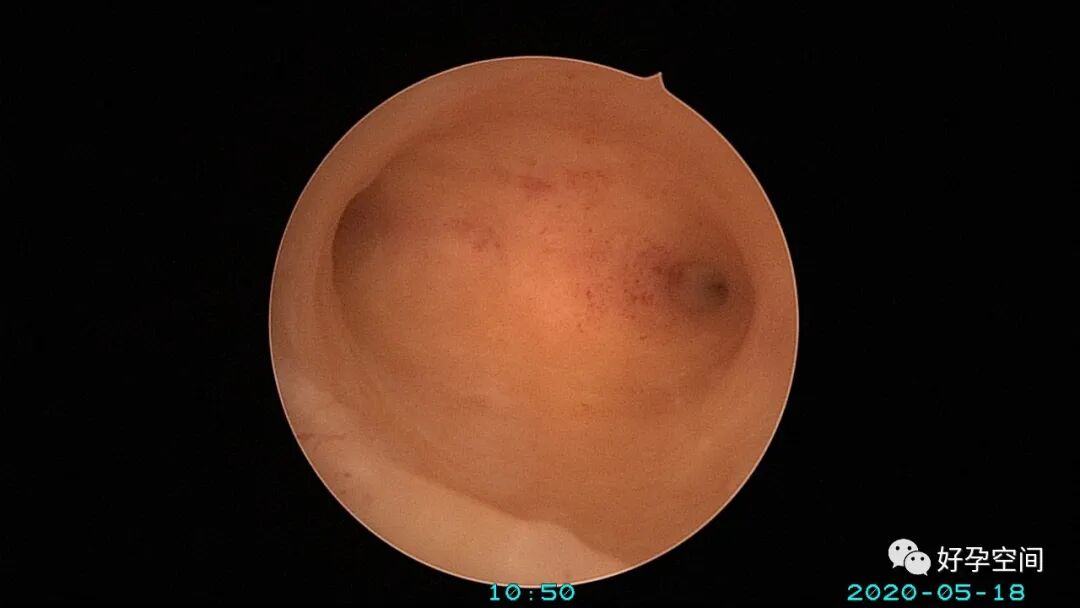

病例3:(病人年龄及取卵个数不详)取卵术后血尿膀胱内血块尿潴留,膀胱灌洗效果不佳,宫腔镜探查膀胱,清除血块,膀胱多处穿刺伤,电凝止血。

病例4:32岁,取卵13枚,取卵术后血尿膀胱内血块尿潴留,膀胱灌洗效果不佳,宫腔镜探查膀胱,清除血块,膀胱底见穿刺伤,电凝止血。